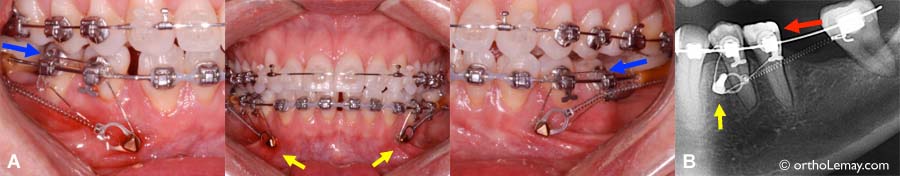

(A) Exemples de mini-vis d’ancrage (flèches jaunes) utilisées pour fermer des espaces inférieurs en avançant les deuxièmes molaires (flèches bleues) à l’aide d’un ressort attaché directement sur les mini-vis (ancrage direct).

(B) Radiographie montrant la mini-vis bien placée dans l’os alvéolaire. La vis est bien placée entre les racines des deux dents mais l’angle de prise de la radiographie peut laisser croire que la vis est très près d’une racine, ce qui n’est pas le cas.